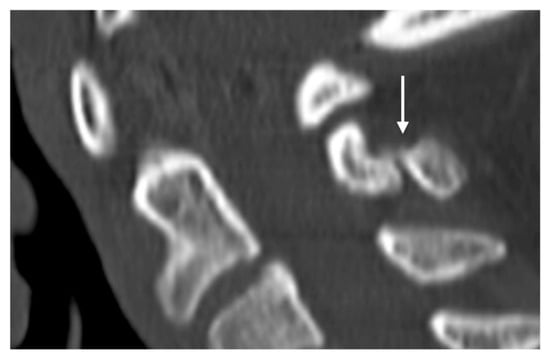

These fractures can be readily visualised on a plain film or CT, where a displaced fragment without a sclerotic edge can be seen. MR demonstrates bone marrow oedema (T2 hyperintensity) at the fracture site with frequent oedema within the interspinous ligament. Chronic non-union is a complication and is characterised by sclerosis and/or irregularity of the fracture line (Figure 8) and by resolution of oedema on MRI.

Figure 8.

Sagittal CT image demonstrating a non-united fracture of C2 spinous process (white arrow).

Spinous fractures also occur due to direct trauma. In most cases, these would be expected to occur with other more significant spinal fractures. However, isolated traumatic spinal process fractures have been described [31,32]. Additionally, osteoporosis is a significant risk factor for spinous process fracture [33]. In the context of trauma, CT is the gold standard imaging modality.